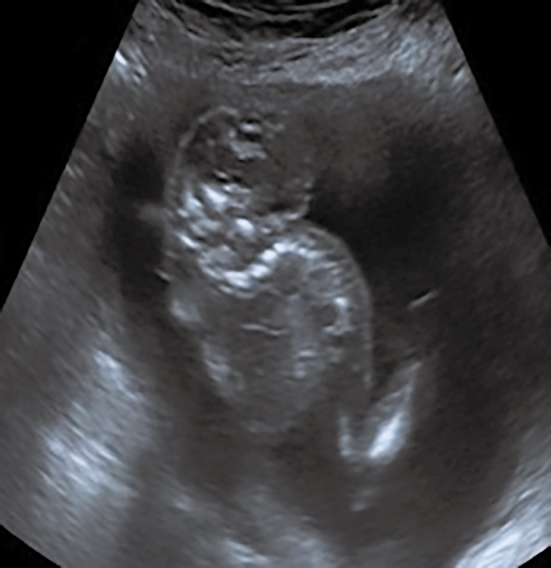

胎儿暴露于丙戊酸的神经管缺陷。

Neural Tube Defects in Fetus Exposed to Valproate.